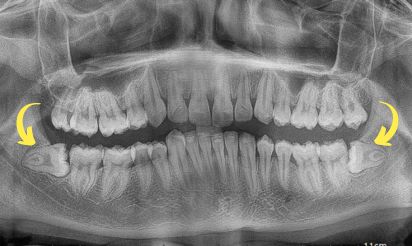

Due to the evolutionary process, the jaw size in humans is decreasing. This has led to reduced space for the last tooth i.e., the wisdom tooth, causing them to erupt in abnormal positions and angles. It can be painful, and there may be increased food lodgement around them. If it is left untreated for a long time, it can lead to infection and swelling, affecting the neighbouring tissues like other teeth and gums.

Being the last in line, sometimes the eruption of wisdom teeth might not be smooth for space constraints. They are misaligned and might also damage the adjacent teeth.

Wisdom teeth can cause misalignment and crowding if they do not get ample space to erupt. There are also chances the tooth might be impacted and might not erupt totally.

Wisdom teeth are bulkier as compared to the other teeth in the oral cavity. The curvature of the wisdom tooth and the level at which they are situated may vary from person to person. Some may be visible above the gums, whereas others may be tilted or embedded within the bone, which makes it difficult to grab them with conventional tools. Earlier in 3% of these extractions, loss of sensation was observed, but thanks to high precision cutting tools available now, drilling around the tooth has become easier. The procedure is more predictable and has reduced the chances of such complications. Following this, the dentist gently elevates the tooth to loosen it up without damaging the adjacent tissues it is removed.

The extraction of a wisdom tooth depends upon how far it has erupted. For a tooth that has fully erupted, the extraction is easier. For the impacted tooth, incisions must be made in the gums. The wisdom tooth is usually extracted in parts to minimise the amount of bone required to be extracted for tooth removal.